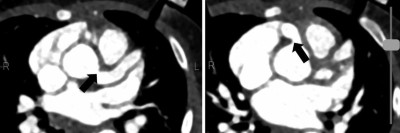

Transkatheter Aortenklappenimplantation (TAVI)/© Boonyakiatwattana W. et al. doi.org/10.1186/s12872-022-02576-y unter CC-BY 4.0, Echokardiografie der Aortenklappe/© Pitchy / stock.adobe.com, Schmerzende livide Areale am Bauch/© A. Frahnert, Aneurysma bei 2-monatigem Säugling mit Kawasaki-Syndrom/© Navidi et al. https://doi.org/10.1186/s13256-024-04987-1 unter CC-BY 4.0, Kanüle für Katheterbehandlung/© romaset / stock.adobe.com, Ärztin führt eine Nierenultraschalluntersuchung durch/© Graphicroyalty / stock.adobe.com (Symbolbild mit Fotomodell), Patient mit perforierter ICD-Tasche/© P. Fleckenstein, Vegetationen der Herzklappe/© Schönfeld L et al. / all rights reserved Springer Medizin Verlag GmbH, Echokardiografische Evaluation der Aortenklappeninsuffizienz/© Digitales Archiv der Uniklinik Köln, Explantierte Prothese nach Transkatheter-Aortenklappenimplantation/© Saha S et al. / all rights reserved Springer Medizin Verlag GmbH, Mitralklappe/© Springer Medizin, Hauteffloreszenzen der rechten Hand/© Marschner M et al. / all rights reserved Springer Medizin Verlag GmbH, Search Icon, Eine ältere Frau riecht an einem Basilikumblatt/© Halfpoint / Stock.adobe.com (Symbolbild mit Fotomodell), Ultraschall bei einem älteren Patienten/© Alex Potemkin / Getty Images / iStock (Symbolbild mit Fotomodellen), Person hält Tablette und Glas/© bilderstoeckchen / stock.adobe.com (Symbolbild mit Fotomodell), EKG befunden mit System - EKG Essential/© Springer Medizin Verlag GmbH